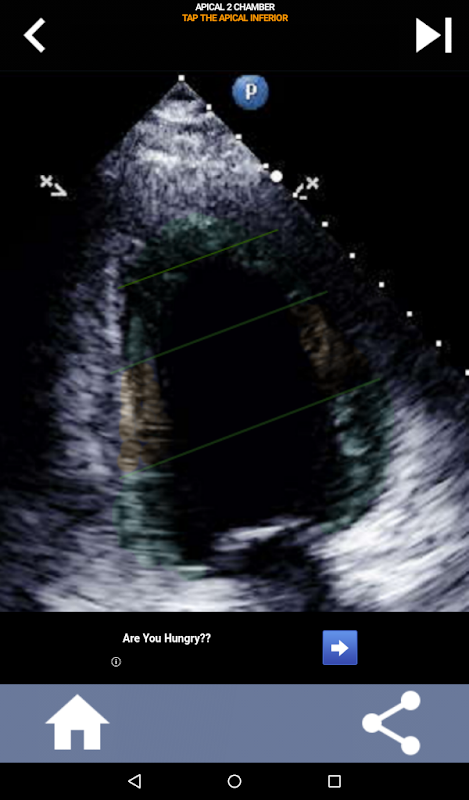

Pendekatan visual berbasis kuis untuk mempelajari segmen jantung AHA: Ekokardiografi

Aplikasi ini akan menguji pengetahuan Anda menggunakan gambar gema yang sebenarnya, yang sering saya temukan sebagai metode pengajaran terbaik.